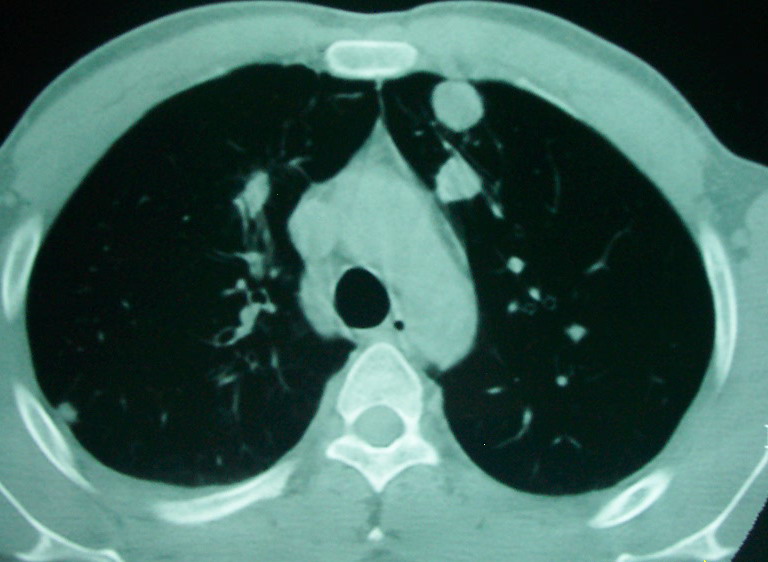

m      37y      发热   咳脓痰月余      ct肺脓肿但住院抗炎治疗后双肺内结节不知该如何解释

治疗后见左肺下野病灶较前缩小但双肺内结节影似无变化请较各位老师该如何下结论    治疗前wbc14.5 治疗后wbc 11.0

如果你仔细的同层面对比,你会发现所有的病灶均有比较明显的吸收、缩小。病变的形态,特别是脓肿的形态、壁的厚薄、内壁均有很大的变化,均在往好的方面发展。与临床症状、血像均符合,治疗效果比较显著,就是肺脓肿并双肺的化脓性炎症灶。